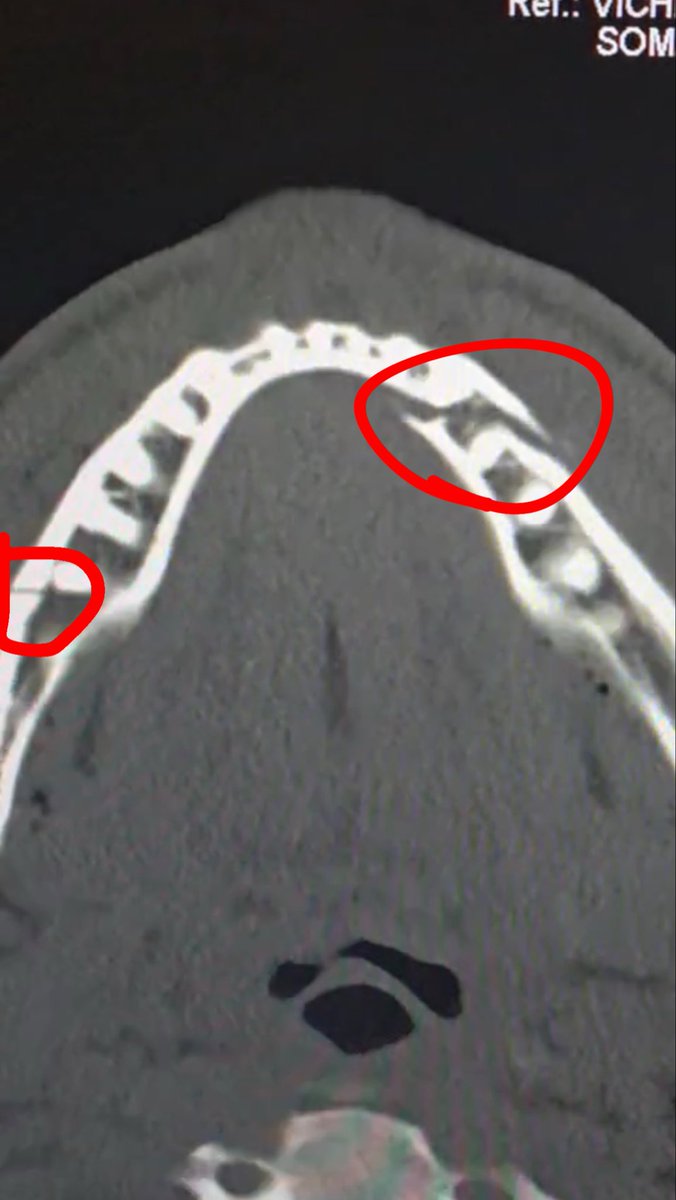

Double broken jaw. Give me Canelo in 10 days.

Just got out of surgery. Everything went smooth. Thanks for all the love. Lots of pain and stiffness. Gotta eat liquids for 7 days S/o to the amazing team at Miami University hospital. Everyone was so gracious and caring. @ArmaniiJayy took amazing care of me with @iam_loriv